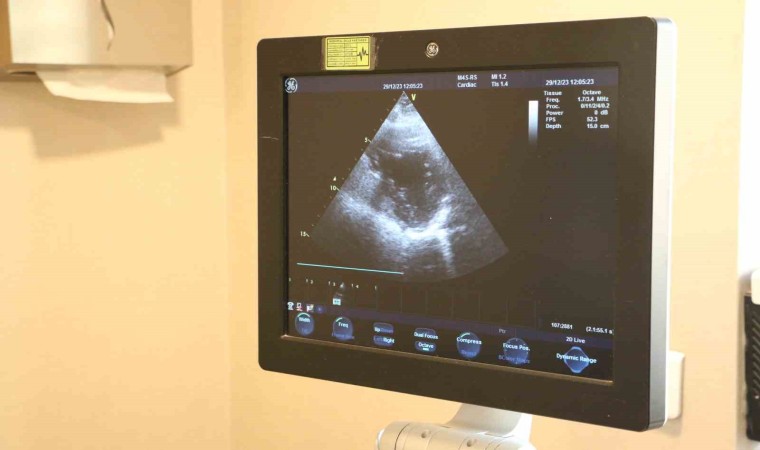

Diyarbakır’da Dicle Memorial Hastanesi’nde Uzman Doktor Hüseyin Akçalı, geçirilmiş kalp krizi sonrası özellikle kalp kapak hastalığını ortaya çıkabileceğini söyledi.

Kalp kapaklarının vücutta 4 tane bulunan, kan akışını sağlayan ve kan akışına yön veren kapaklar olduğu bilgisini veren Dr. Akçalı, "Kalp kapak hastalıkları, zamanla yaşa bağlı olarak ortaya çıkabileceği gibi geçirilmiş enfeksiyona bağlı konjenital olarak ya da travmaya bağlı ortaya çıkabilir. Geçirilmiş kalp krizi sonrası da kalp kapak hastalığı ortaya çıkabilir. Kalp kapak hastalıklarının belirtileri; halsizlik, çabuk yorulma, nefes darlığı, ayaklarda şişkinlik olarak nitelendirebiliriz temel olarak, baş dönmesi, baygınlık. Bunlar kalp kapak hastalığının belirtileri olabilir” dedi.